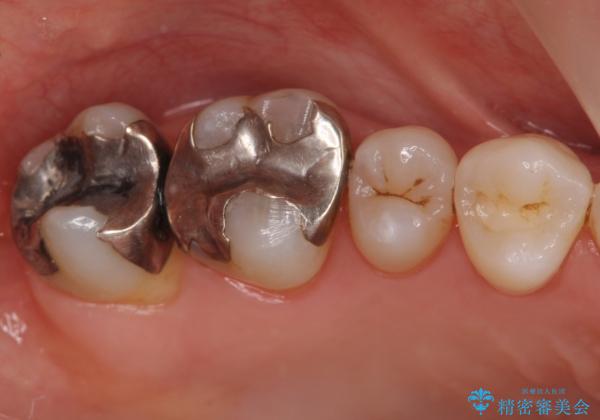

- 銀歯を白くしたいとのことで来院されました。

銀の詰め物を除去した後、その奥にある古い詰め物も除去し完全にむし歯を取り切ったことを確認してからセラミッククラウンを装着していきます。